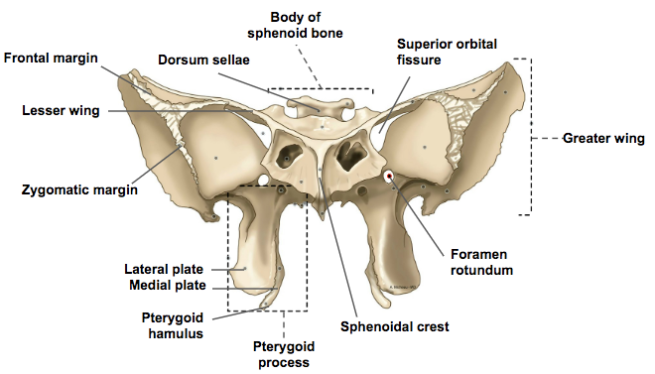

Sphenoid bone

-

pterygoid hamulus

-

Foramen rotundum

-

Foramen ovale

-

Foramen spinosum

-

Pterygoid canal

-

Foramen lacerum (破裂孔)

-

Optic canal

- CN II

- Ophthalmic a.

-

Sup. orbital fissure

- Ophthalmic n.(CN V1)/ v.

- CN III, IV, VI

相鄰骨

F, O, T, E, Pr, V, Z, Pl, Mx

上視圖

前視圖

後視圖